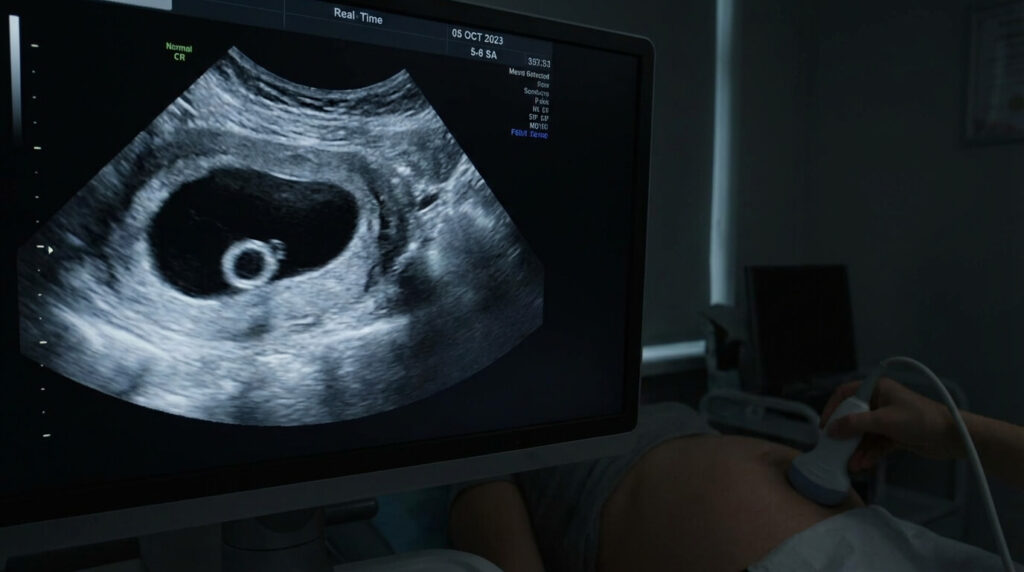

L’échographie de datation précoce (avant 8 semaines) est un moment chargé d’émotion, mais parfois source d’angoisse intense. Le gynécologue ou la sage-femme observe le sac gestationnel, confirme la présence de la vésicule vitelline (ce petit anneau blanc nourricier), mais annonce qu’il ne voit pas encore d’embryon ni d’activité cardiaque. Ce verdict en demi-teinte plonge les futurs parents dans l’incertitude. Est-ce une grossesse arrêtée (œuf clair) ou simplement une grossesse plus jeune que prévu ? L’interprétation de cette image dépend de critères millimétrés et nécessite souvent de la patience.

- 🥚 Le rôle : La vésicule vitelline est la première structure visible dans le sac (vers 5 SA). Elle nourrit l’embryon avant que le placenta ne prenne le relais. Sa présence confirme que la grossesse est intra-utérine.

- 5 à 5,5 SA : La vésicule vitelline apparaît. C’est un petit rond blanc à l’intérieur du sac. C’est un très bon signe, cela exclut l’œuf clair « total » (sac vide dès le départ).